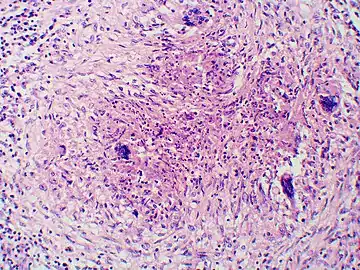

Once suspected, the diagnosis of blastomycosis can usually be confirmed by demonstration of the characteristic broad based budding organisms in sputum or tissues by KOH prep, cytology, or histology.[27] Tissue biopsy of skin or other organs may be required in order to diagnose extra-pulmonary disease. Blastomycosis is histologically associated with granulomatous nodules.

Granuloma with early suppuration. Fungal organisms difficult to recognize at this low magnification. Granuloma with early suppuration. Fungal organisms difficult to recognize at this low magnification.

Large yeast-like fungi seen within giant cells at arrows. Large yeast-like fungi seen within giant cells at arrows.

Large yeast-like fungi seen within giant cells at arrows. Budding yeasts in cytoplasm of giant cells at arrows. Broad-based budding and double contoured cell wall seen in the giant cell in the center is characteristic of Blastomyces dermatitidis. Large yeast-like fungi seen within giant cells at arrows. Budding yeasts in cytoplasm of giant cells at arrows. Broad-based budding and double contoured cell wall seen in the giant cell in the center is characteristic of Blastomyces dermatitidis.